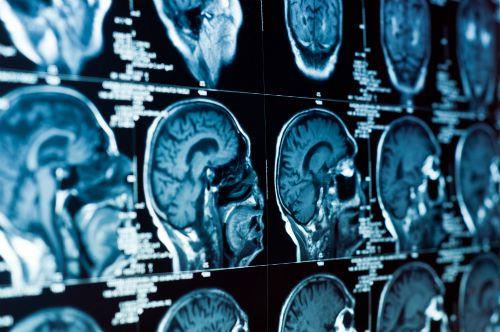

לא רק בלב: לחץ דם גבוה פוגע גם במוח

ידוע לכל כי לחץ דם גבוה עשוי להוביל להתקף לב, אולם גם המוח נמצא בסכנה. כיצד יתר לחץ דם לא מאוזן מעלה את הסיכוי ללקות בשבץ מוחי, שיטיון ואלצהיימר?

הוא מכונה "הרוצח השקט": יתר לחץ הדם יכול לפגוע בנו קשות גם מבלי שיתרחש אירוע חד ודרמטי כמו התקף הלב או שבץ מוחי, אך גם בהתדרדרות קוגניטיבית איטית כאלצהיימר ושיטיון. כל חלקי גופנו תלויים באספקת הדם שמגיעה אליהם ונפגעים כתוצאה מיתר לחץ דם לא מאוזן, גם אם אנחנו לא מודעים למחלה. אחד האיברים שנמצא בסיכון הגבוה ביותר להיפגע הינו המוח.